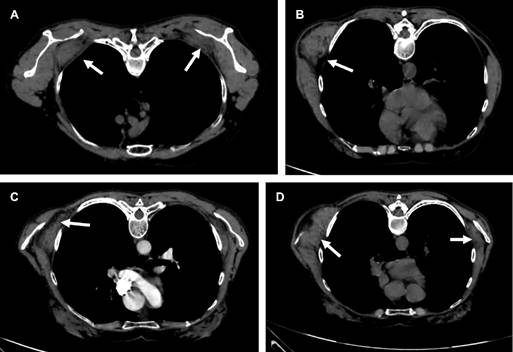

Paciente femenino de 60 años, ama de casa, acude por presentar abultamiento de cinco años de evolución en región escapular derecha, que le ocasiona discreta molestia al efectuar limpieza en el hogar. A la exploración se observa masa de consistencia ahulada en ángulo inferior de escápula derecha prominente, con dimensiones de 7 × 5 cm (Figura 1A-C), no dolorosa al movimiento, con sensación de frote a los desplazamientos de ambas escápulas, con arcos de movilidad de hombros completos y sensibilidad normal; el resto de la exploración es normal. Con diagnóstico presuntivo de elastofibroma dorsi. Se solicita tomografía computarizada (Figuras 1 a 3) que confirma elastofibromas dorsi bilaterales; se propone cirugía, la cual rechaza.

La ecografía, la tomografía computarizada y la resonancia magnética confirman el diagnóstico.4 En la ecografía se observa un patrón alternante, de tipo fasciculado o laminar, de líneas hipo e hiperecogénicas paralelas a la pared torácica; la señal Doppler suele ser negativa. La TC muestra alternancia de tejido adiposo con densidad grasa y de tejido fibroso con densidad muscular, que no realza con medios de contraste. La resonancia magnética es de elección para llegar al diagnóstico presentando patrón alternante de tejido adiposo y fibroso; en T1 y T2 el tejido fibroso da señales de baja intensidad similares a las del músculo. El tejido adiposo da señales de alta intensidad en T1 y señales intermedias en T2. La biopsia se reserva para los casos sospechosos que no presentan el patrón característico.5